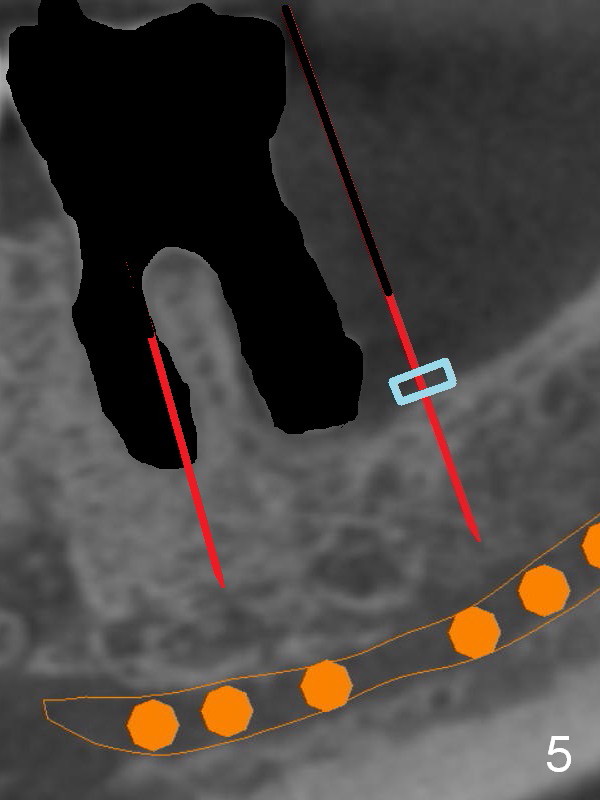

There is severe bone resorption around the distal root of the lower left 1st molar of the 56-year-old man (WG), while the loss of the 2nd molar is associated with limited bone height (Fig.1). A 5x14 mm implant will be placed at the mesial socket of #19 and 5.9 or 6.4x6 mm one is at the mesial site of #18 (Fig.7-9). Use a 2 mm pilot drill with 6 mm stopper from Sinus Master Kit (with extension) to initiate osteotomy at #18 immediately distal to the crown of #19, parallel to the long axis of the latter (Fig.2). After inserting a parallel pin at #18, extract the tooth #19 (Fig.3, antibiotic pending) and start osteotomy with a 2 mm pilot drill with 14 mm stopper (Fig.4). Insert the calibrated parallel pin at #19 (Fig.5) and measure the distance between the two parallel pins (approximately 10 mm, Fig.7). Sequential osteotomy and application of the Tatum taps (Fig.6 red rectangle) will push the septum distal (green arrow). As to #18 osteotomy, trephine, final and tap drills are to be used with control of the depth: 6 mm (Fig.7,9).